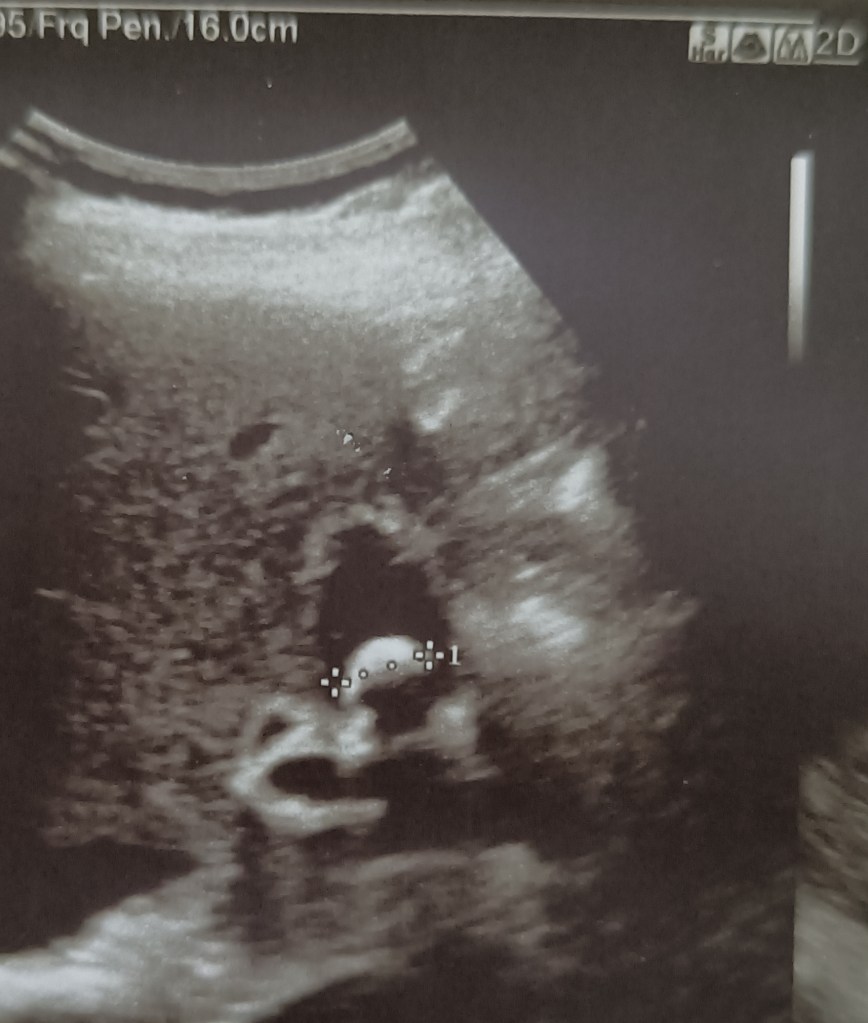

A 35 years old female presented with pain RUQ, and found, on ultrasound scan, to have a 1.5 cm stone in the residual gallbladder (h/0 lap chole 2.1.2020) which was smaller and rotund in shape. During the previous operation, the patient had some symptoms 10 days after LC, and found to have a 45-60 ml collection, which resolved with time. At operation, there were dense omental adhesions with the liver in the gallbladder fossa. After this area was cleared, a small residual gallbladder was found with a stone inside. The stone was first removed and the Calot’s triangle cleared to define the CA and CD with difficulty.